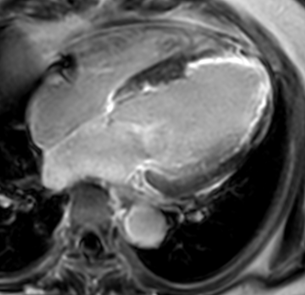

心臓MRIは、強力な磁石と磁気の力を使って心臓や血管を撮影する検査です。放射線被曝がないため、繰り返し検査を受けることができます。

また、⾝体の輪切り(横断像)だけでなく、あらゆる⾓度の断⾯像を得ることができ、⼼臓の機能や形態、冠動脈、⼼筋組織性状、⼼臓や⾎管などを総合的に評価できる有⽤な検査です。

当院では、高画質MRI装置(PHILIPS Ingenia Elition 3.0T)を使用しており、検査中の不安やストレスをできる限り軽減できるよう努めています。

T2強調画像

心臓内の血流信号を抑制し、左室内腔の血液信号を低信号とすることで、心臓の構造を評価することができます。心筋の浮腫や炎症性変化を捉えることができ、急性~亜急性期心筋梗塞や心サルコイドーシスの活動性病変部の検出に有用とされています。